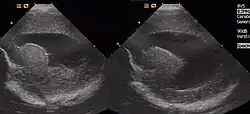

Die Kolpozephalie (von altgriechisch κόλπος kolpos ‚Scheide‘ und altgriechisch κεφαλή kephalie ‚Kopf‘) ist eine abnormale Form des Seitenventrikels mit überproportionaler Erweiterung des Hinterhornes (Cornu posterius/occipitale) bei schmalem Vorderhorn (Cornu anterius/frontale).[1][2]

Die Diagnose ergibt sich aus der Bildgebung meist zunächst mit Sonographie, ggf. zusätzlich mit Magnetresonanztomographie zur Erfassung von Heterotopien. Sie kann bereits pränatal gestellt werden.[9]